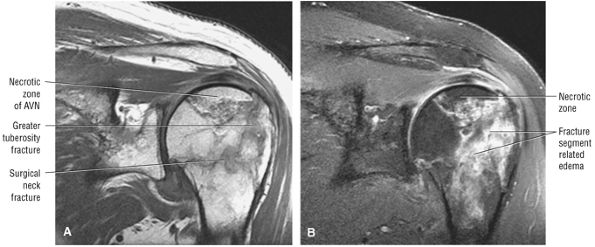

FIGURE 8.102 ● (A) The anterior undersurface of the acromion and the coracoacromial ligament form the coracoacromial arch. The subacromial subdeltoid bursa facilitates the passage of the rotator cuff and proximal humerus under the coracoacromial arch. (B) A superior axial image shows the anterior-to-posterior extent of the coracoacromial (CA) ligament perpendicular to the supraspinatus tendon. The fluid in the subacromial-subdeltoid bursa represents fluid between two serosal surfaces in contact with each other. One serosal surface is contributed by the undersurface of the coracoacromial arch and deltoid, and the other serosal surface is on the bursal side of the cuff.

|

![]() |

FIGURE 8.103 ● Pseudospur. The normal broad attachment of the coracoacromial ligament to the inferior surface of the acromion is shown on (A) T1-weighted coronal oblique and (B) sagittal oblique images. The low-signal-intensity acromial cortex (black arrows) and adjacent coracoacromial ligament and lateral slip of the deltoid attachment (white arrows) give the false impression of a small subacromial spur in the coronal plane. This pseudospur should not be misinterpreted as impingement; otherwise, unnecessary acromioplasties may be performed on patients with a normal coracoacromial ligament attachment and no associated acromial spurs.